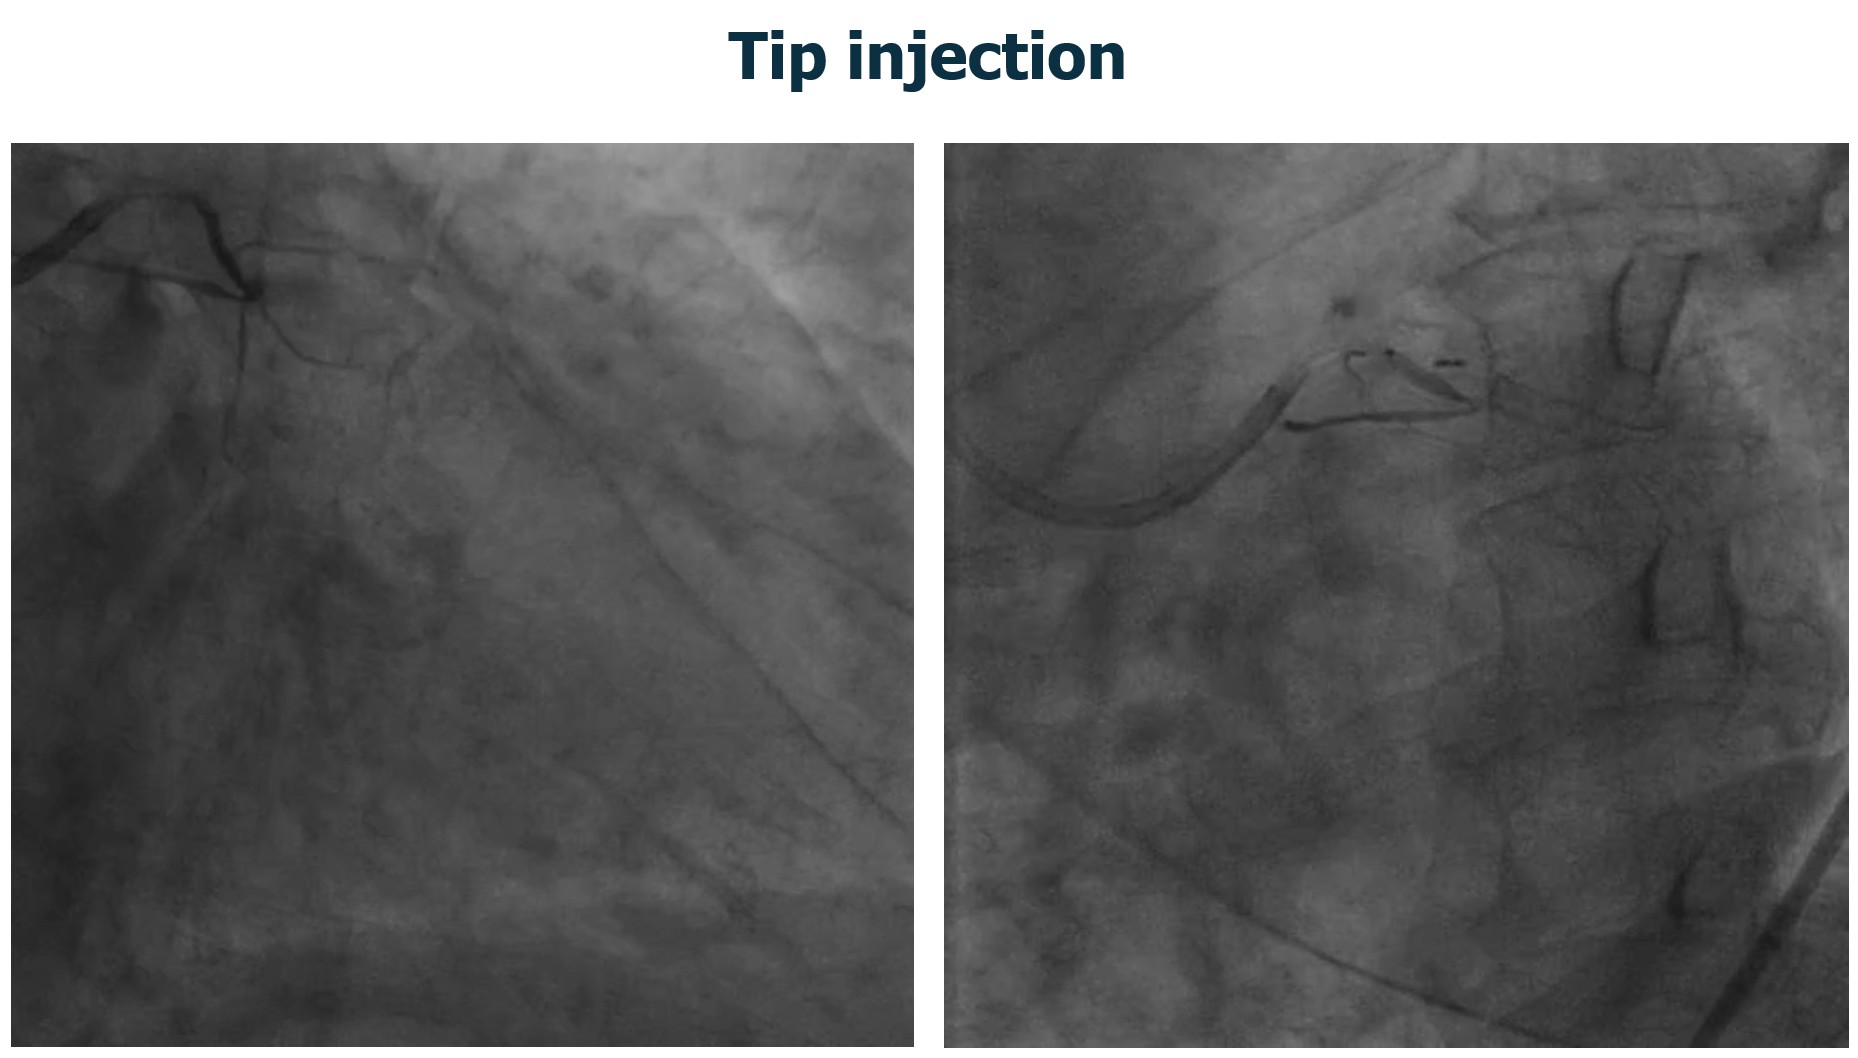

Coronary angiography demonstrated patent prior RCA stents. The LCX CTO had a J-CTO score of 3 (ambiguous proximal cap, calcification, and prior failed attempt). Distal LCX was opacified via epicardial collaterals from the PL branch. Antegrade tip injection failed to reveal bridging collaterals or a definable micro-channel for entry, making antegrade crossing unfavorable.